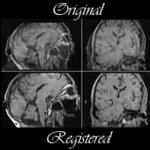

SPL Automated Segmentation of Brain Tumors Image Datasets. |

SPL Brain Tumor Resection Image Datasets |